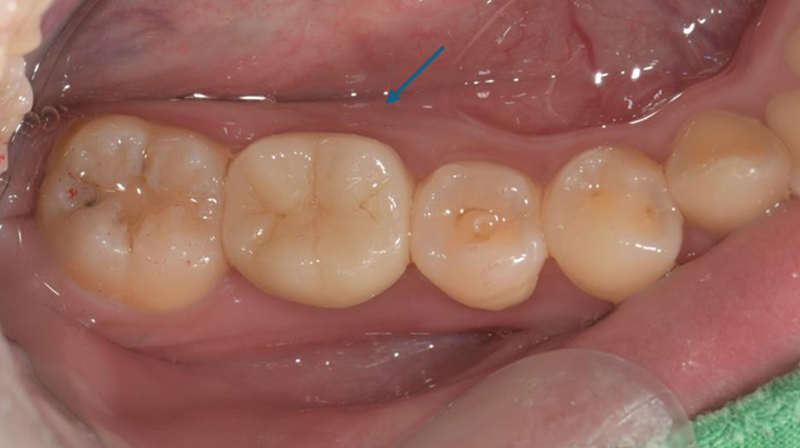

術後完成假牙裝戴

牙齒狀況改善

術後